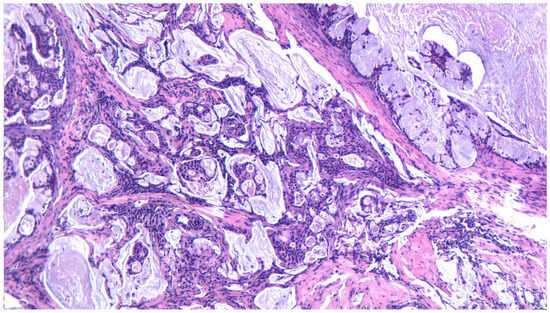

3.2. Pleomorphic Adenoma

3.10. Adenocarcinoma